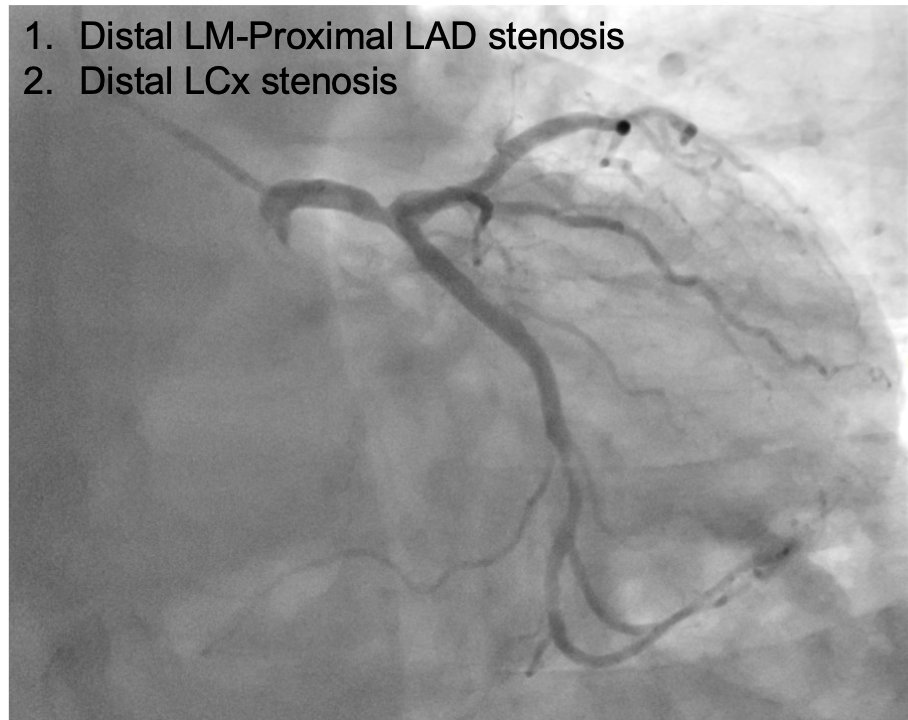

Our #RPCI program started one year ago in @CardioAalst. Reaching the milestone of 100 procedures with an unprotected left main R-PCI in a same day discharge setting. @EricWyffels @bertolone_dario @ColletCarlos @jeroen_sonck @BernardBruyne @EAPCIPresident #teamwork